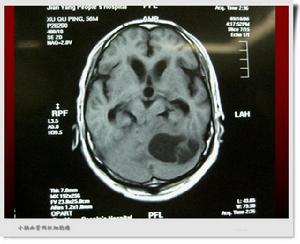

血管網狀細胞瘤CT圖血管網狀細胞瘤占所有腦腫瘤的1.5%~2%,占後顱窩腫瘤的7%~12%,好發於小腦半球,中國外資料顯示發生在小腦半球者占62.3%~80%,其次可發生在小腦蚓部或突入第四腦室顱後窩小腦占80%小腦蚓部13%第四腦室7%。腫瘤居於幕上者僅占12%左右,可見於額葉、顳葉,也可見於腦幹、丘腦及脊髓。而小腦半球中右側多於左側。據報導從新生兒到80歲均可發病,但以青壯年為多,30~40歲最易患病。男性稍多於女性。約6%的視網膜血管瘤病人伴發小腦的血管網狀細胞瘤,而小腦的血管網狀細胞瘤中約20%伴發有視網膜血管瘤。

血管網狀細胞瘤病理圖腫瘤肉眼觀察可為囊性或囊實性,也有實質腫瘤囊性變者。腫瘤境界清,紫紅色,質較韌,直徑大小不一,同腦組織關係密切切面呈暗紫色。鄰近腦膜可有血管擴張。可有棕黃色的含鐵血黃素沉積於囊壁和腫瘤結節內。腫瘤呈囊性者占80%,特別是小腦血管囊性變者更多見。囊內含黃色或黃褐色液體,多在10~100ml之間。囊液蛋白含量較高,易凝固成膠凍樣。測定囊液蛋白質含量每100ml可達3~4g,系腫瘤滲出液腫瘤囊腔內壁光滑,有一富於血管的瘤結節,1/4腫瘤為實質性血運極為豐富如血竇樣紅色瘤結節突入囊內約2cm大小,但有些瘤結節小於1cm,有些甚至隱藏於囊壁內,不易被發現實體腫瘤多較大個別的直徑可達10cm,呈紫色鮮紅色、黃色質軟,血運豐富易出血,與周圍腦組織分界清楚。大多數病例為單發性腫瘤少數病例可有多個腫瘤分布於腦的不同部位。